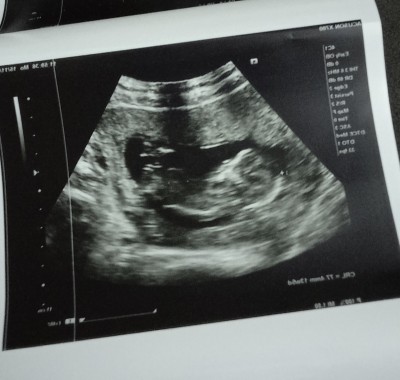

13 haftalık fotoğrafı bu 4 gün sonra tekrar gidecegim

Gebelik haftası 15+4

Nub teorisine gore genital yukari cıkıntılı buda erkege benzerlik konusunda %75 dogru cikiyo  bnde hamileyim oglusumun ultrason fotosuna bnziyo 12+3te ogrenmistim cinsiyetini suan 14+5 olduk

Ilk günden beri bende oglanmis gibi hissediyorum ama daha henüz doktorum bisi demedi ondan arada kaldım 13 haftalıkken gitmiştim bunu vermişti şuan 15 +4 düm 22 sinde yine randevum var belki soyler

bak buda bnim oglusumun ultrasonu burda 13+5  haftalik